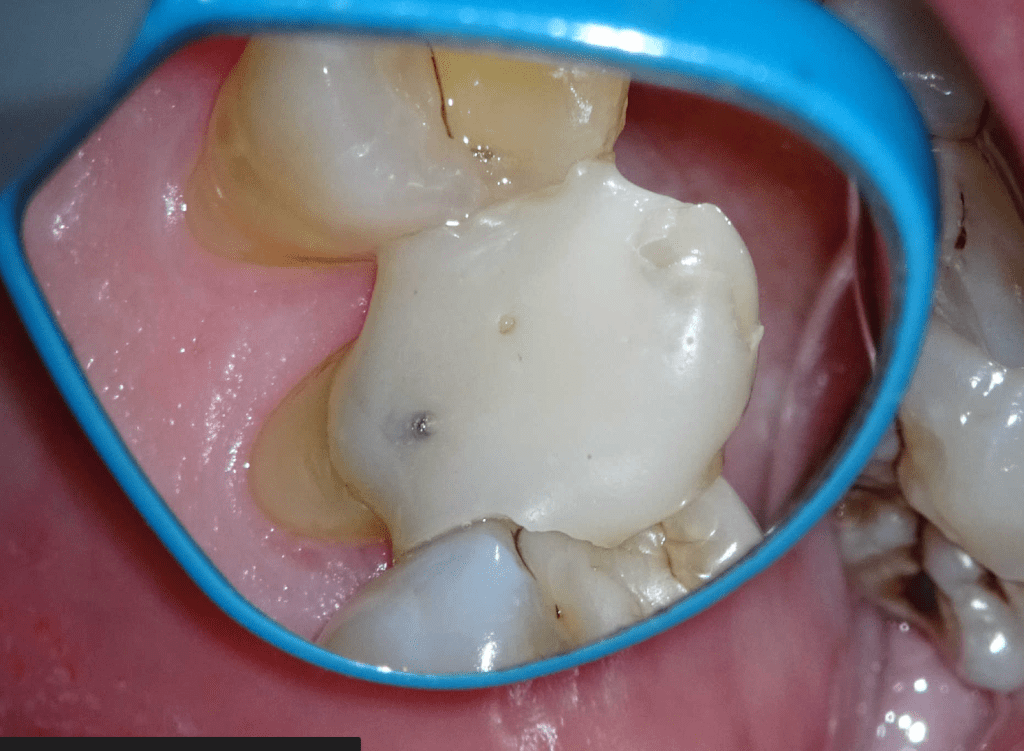

Pulpotomía biodentine + reco preendio